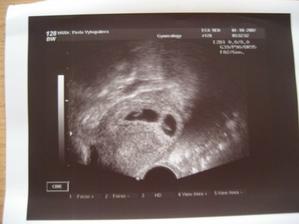

Za dva dny jsem prubla další... no a pak ještě jeden pro sichr opět po dvou dnech ... Jsou sice všechny slabé,ale jsou tam!!! (viz.obrázek) K MUDr.jdu AŽ 1.10. tak snad bude vše v pořádku.. 🙂 Tak dneska 1.10. mi MUDr. oznámila, že vše je vpořádku na 200% (nejdřív jsem to nepochopila,tak mi to musela říct polopaticky)... jsou tam dvě berušky!!! byl to šok... a pro partnera ještě větší.. Obě jsou v pořádku, srdíčka bijou jak mají .. 🙂) tak snad to zvládneme 🙂) Dneska, 2.1.2008, jsme byli na Kardio, srdíčka máme v pořádku a už taky víme, co v bříšku nosíme... 🙂 4.1.2008 jsme byli mrknout na kluky na velkém UTZ, vše O.K. teď už jen ať vydrží v teploučku co nejdéle...